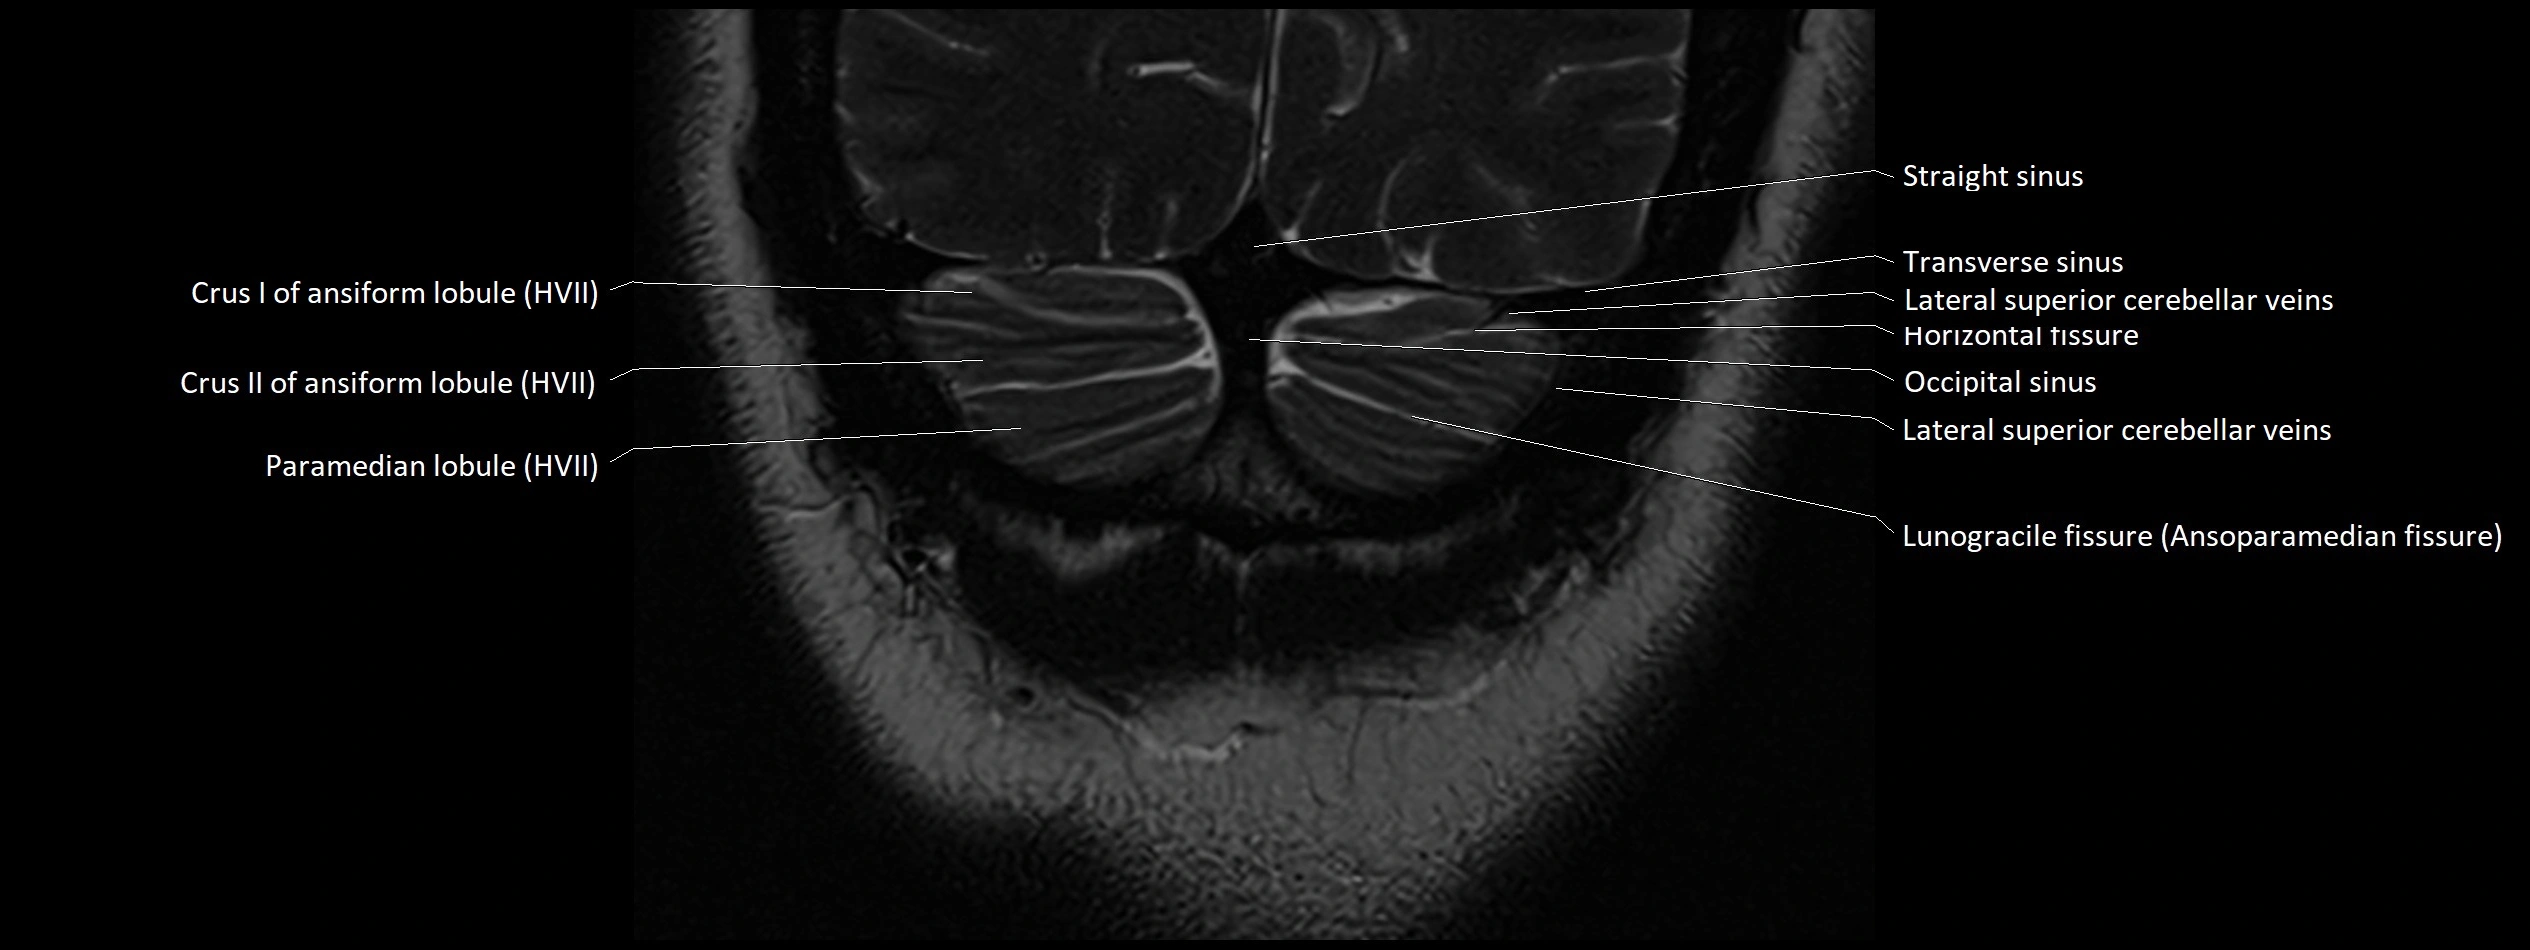

MRI images